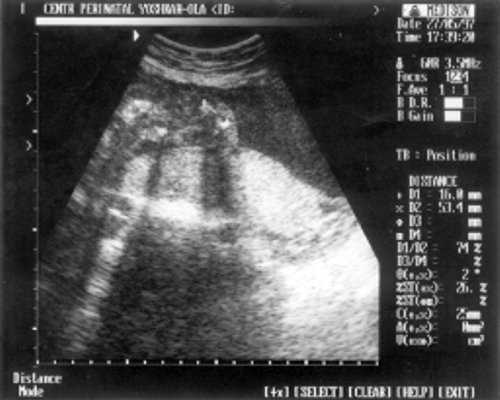

Данные фетометрии:

- (бипатериальный размер головы - от виска до виска) = 65 мм - 26 нед.,

- ОкГ (окружность головы) = 244 - 26 нед. + 3 дня.

- МРМ (межполушарный размер мозжечка) = 25,6 мм - 23,5-24 нед. (рис. 1)

- ОкГрК (окружность грудной клетки) = 42 мм - 19,5 нед.

- ОЖ (окружность живота) = 182 мм - 22 нед. + 6 дн.

- ДБ (длина бедра) = 24 мм - 17 нед. (рис. 2)

- Плечевая кость = 16 мм - 14,5 нед. (рис. 3)

- Кости предплечья = 17,5 мм - 15,5 нед. (рис. 4)

- Малая берцовая кость = 22 мм - 18,5 нед.

- Большая берцовая кость = 24 мм - 18,5 нед.

Рис. 1. УЗИ плода - голова.

Рис. 2. УЗИ плода - бедро.

Рис. 3. УЗИ плода - плечевая кость.

Рис. 4. УЗИ плода - кости предплечья.